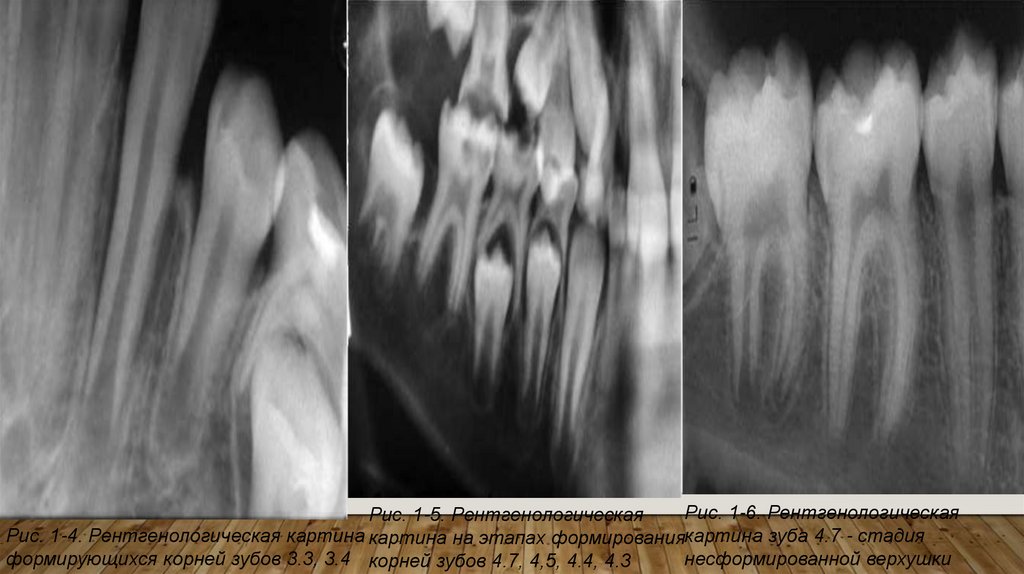

Рис. 1-6. Рентгенологическая

Рис. 1-5. Рентгенологическая

Рис. 1-4. Рентгенологическая картина картина на этапах формированиякартина зуба 4.7 - стадия

несформированной верхушки

формирующихся корней зубов 3.3, 3.4 корней зубов 4.7, 4,5, 4.4, 4.3

Стадия несформированного корня. Рост корня в длину не закончен. При этом стенки корня

идут параллельно и расходятся, образуя «раструб», просвет канала широкий, у «раструба»

переходит в ростковую зону - участок просветления, имеющий округлую форму с четкими

контурами .

Стадия несформированной верхушки. Длина корня достаточная, стенки корня у верхушки

истончены, расходятся, образуя «раструб», четко определяется ростковая зона.

Стадия незакрытой верхушки. Корень нормальной длины, верхушка корня заострена,

апикальное отверстие широкое, ростковая зона не видна.